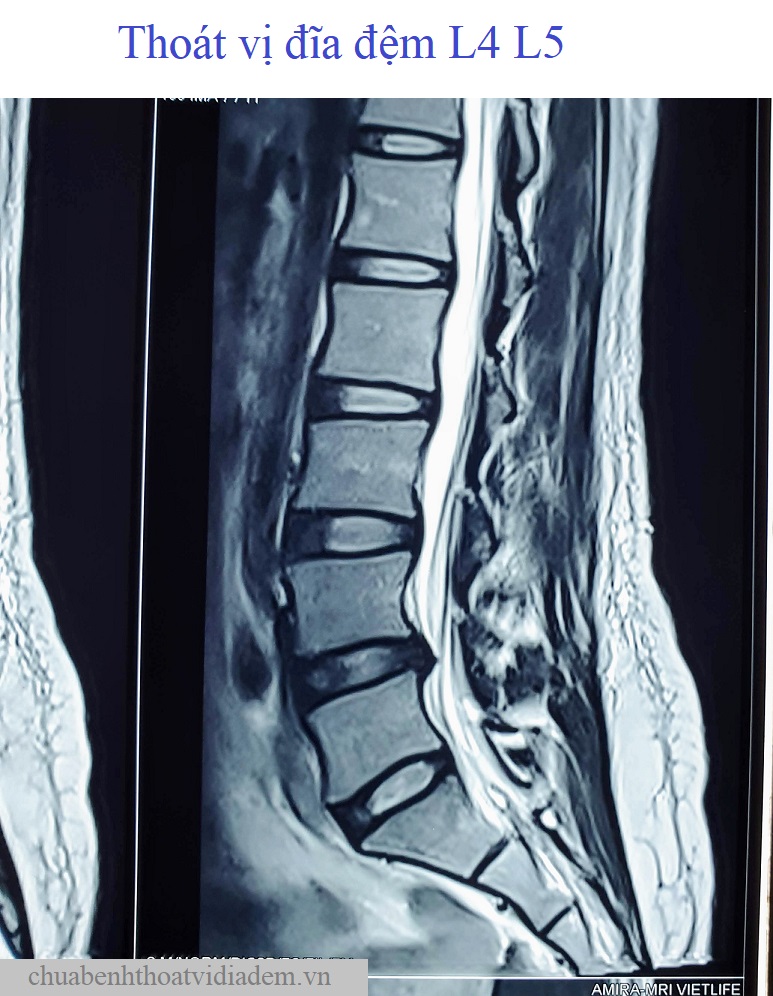

Thoát vị đĩa đệm L4 L5Thoát vị đĩa đệm L4 L5, kích thước 6mm, chèn ép vào rễ thần kinh L5 hai bên và gây hẹp ống sống (đường kính trước - sau #6mm)❮ đọc tiếp ❯